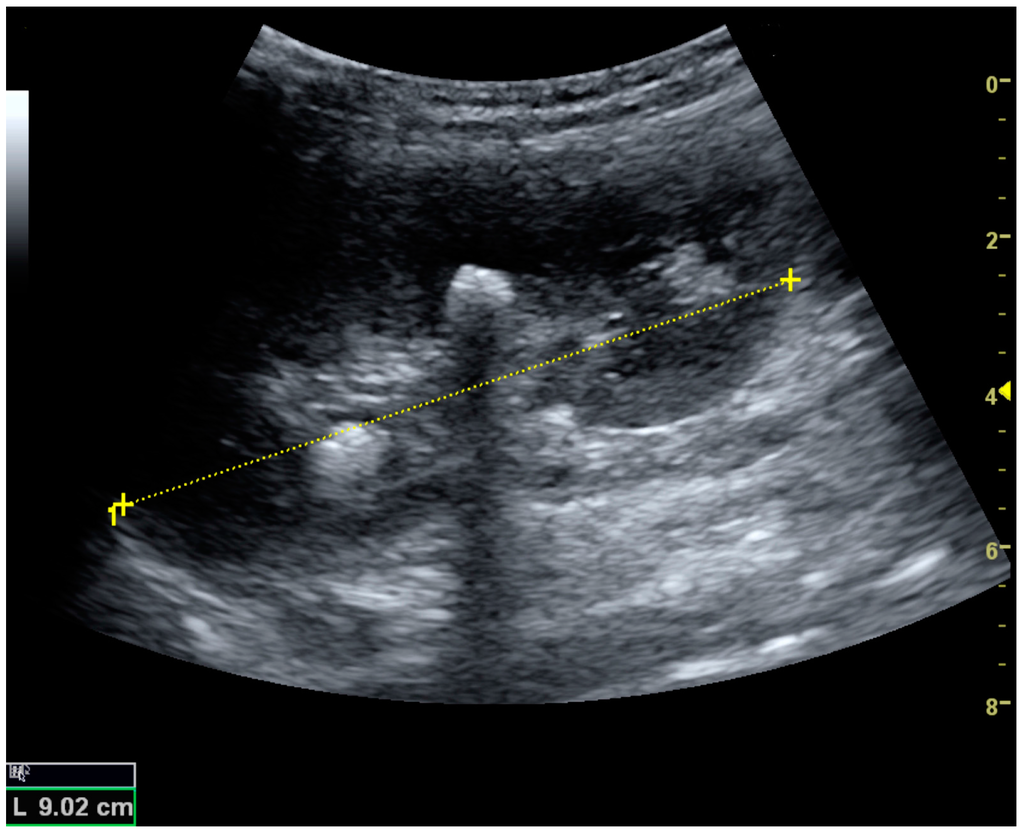

Figure 5. Simple cyst with posterior enhancement in an adult kidney. Measurement of kidney length on the US image is illustrated by ‘+’ and a dashed line.